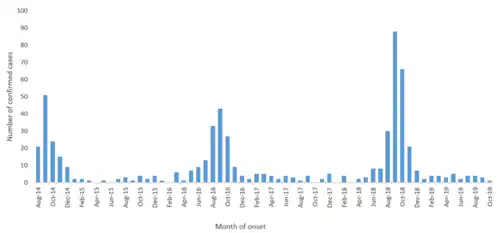

A seasonal pattern is seen in outbreaks, with a marked increase in cases reported in the late summer and early fall.[25]

AFM has only been formally tracked since 2014, since the incidence has spiked in recent years.

CDC sees 2018 as a record year, annual documented cases of AFM reached a record 238 nationwide. The relatively lower circulation in 2020 may reflect the use of COVID-19 pandemic infection mitigation measures.[17]